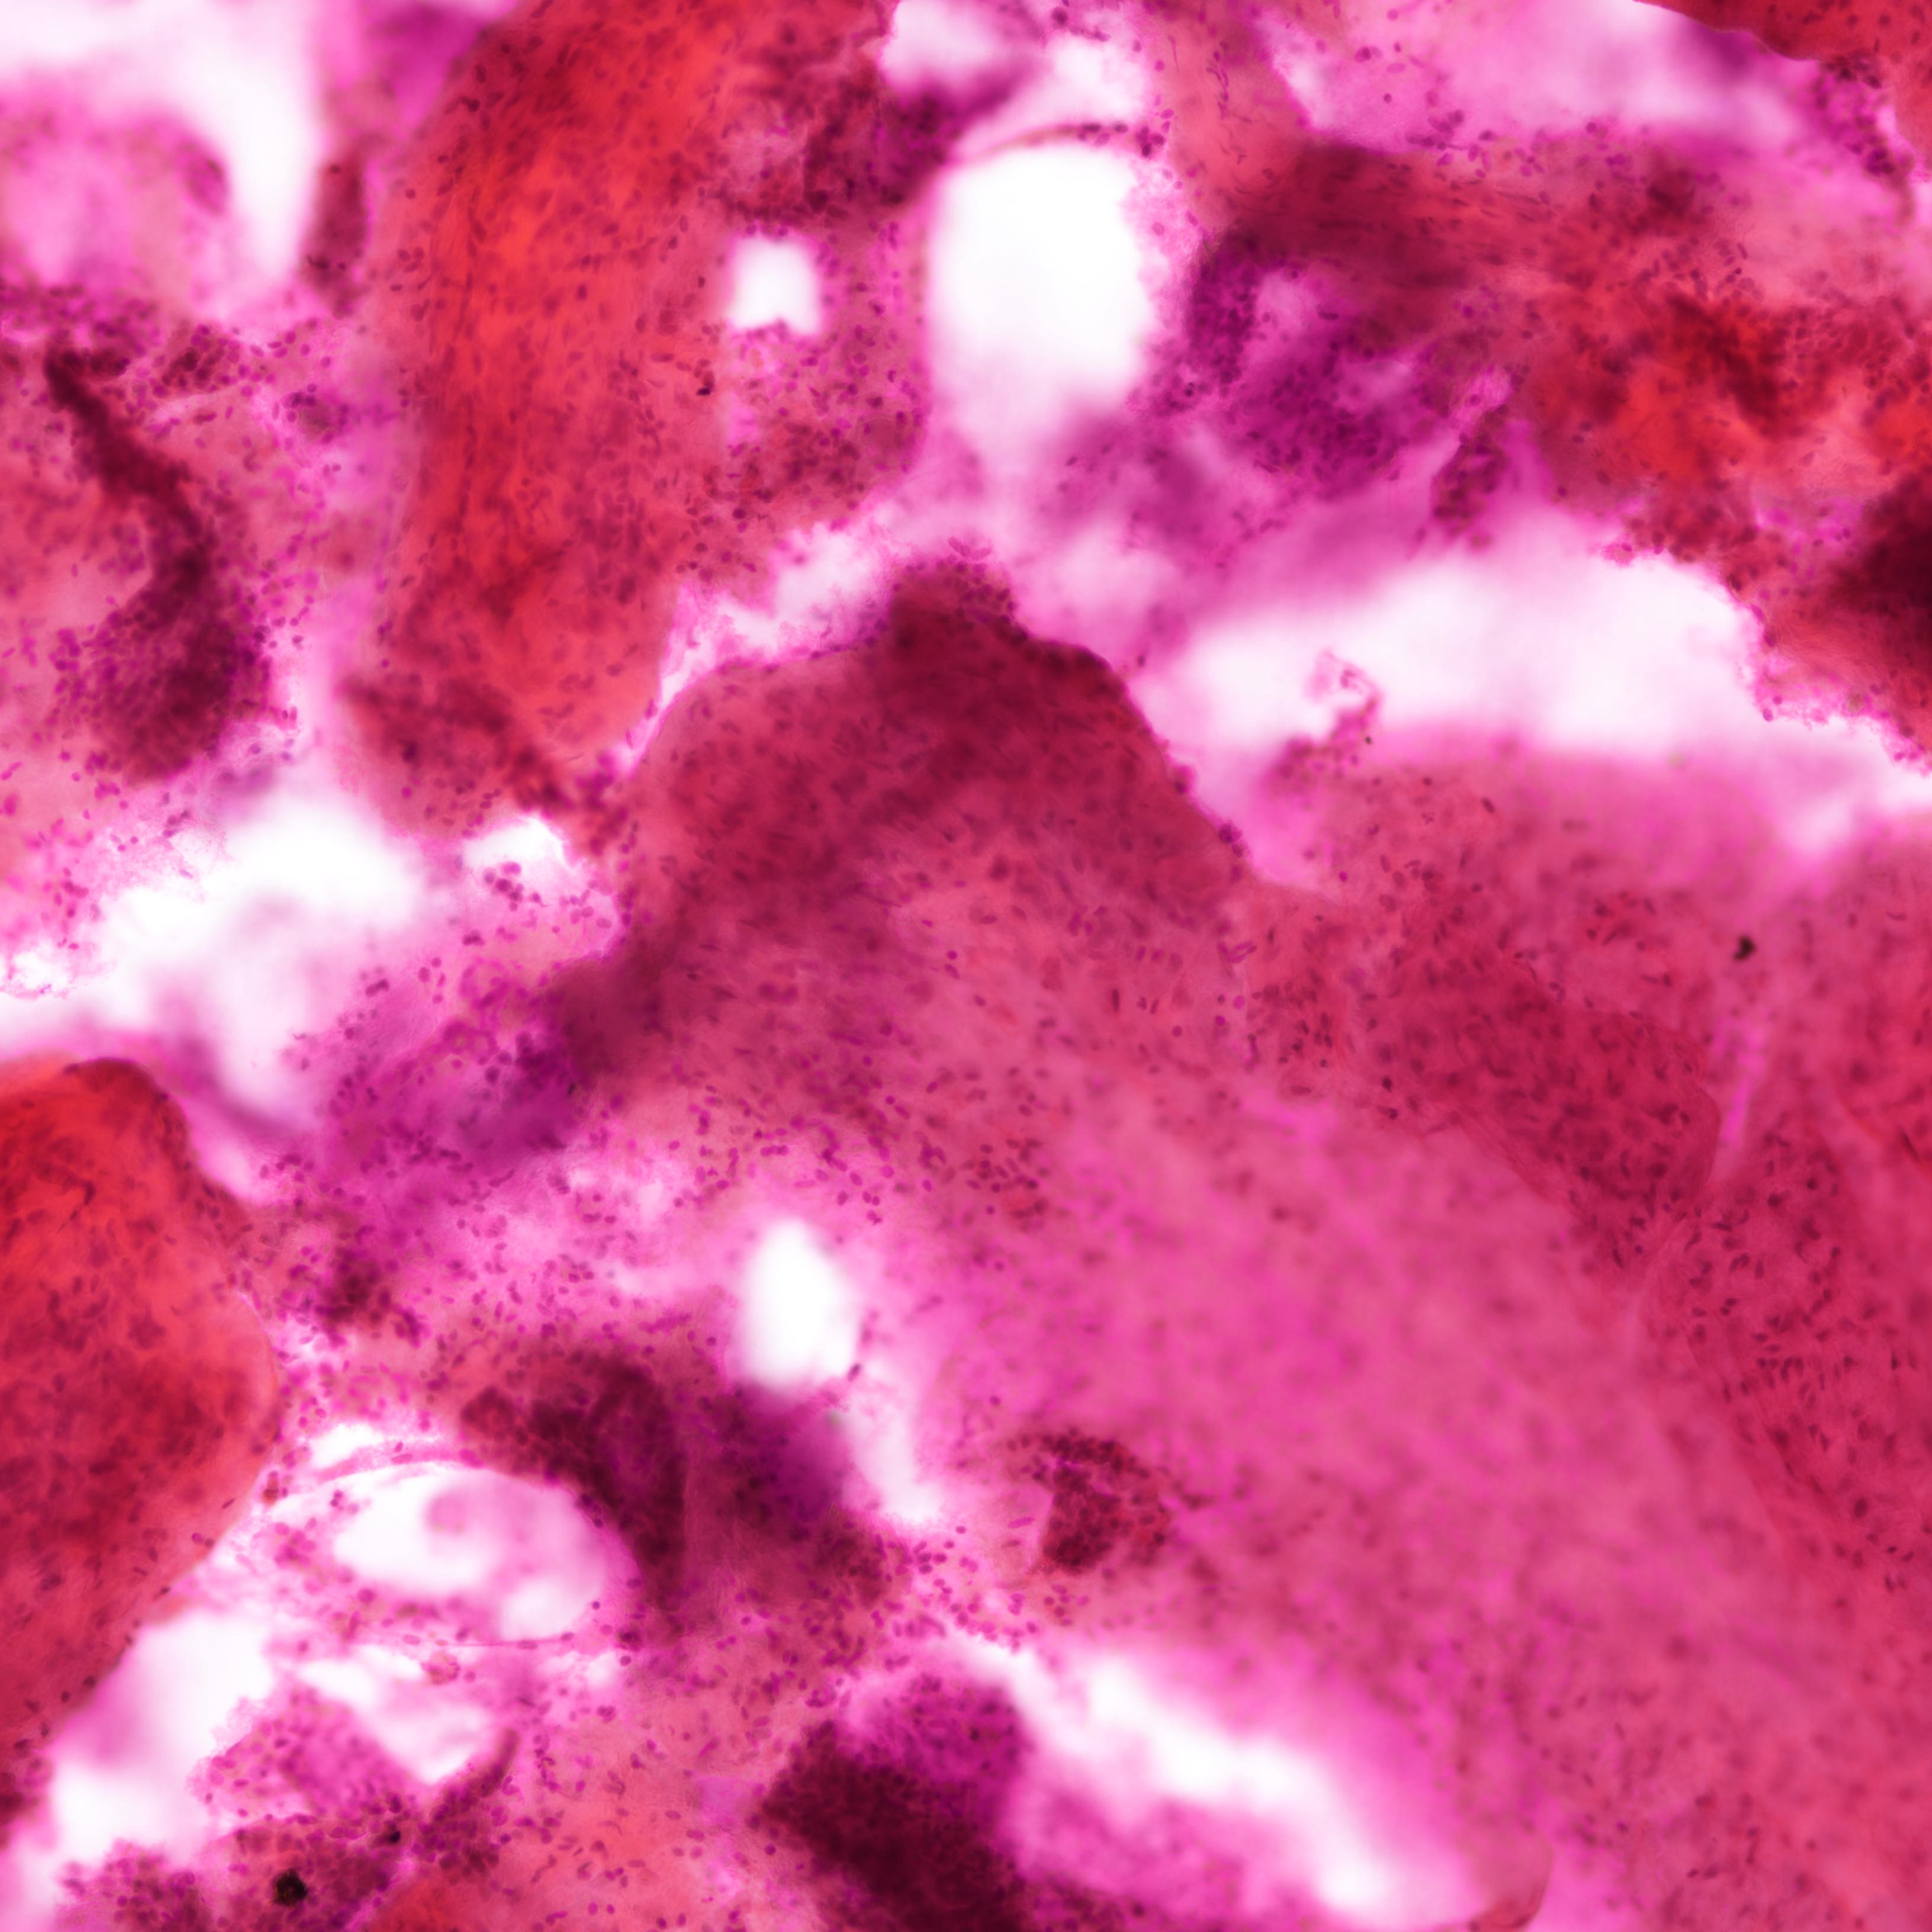

Cytology description

- Fibromyxoid stromal clumps

- Reduced epithelial stromal ratio compared with fibroadenomas

- Higher nuclear atypia and cellularity in phyllodes tumor of higher grades

- Large wavy and folded epithelial clusters

- Usually exhibits benign cytomorphology

- Occasionally, hyperplastic changes with enlarged and vesicular nuclei and small visible nucleoli may be seen

- Fibroblastic pavements

- Increased atypia in dispersed cells in phyllodes tumor of higher grades (Cancer Cytopathol 2010;118:33)

- Multinucleated tumor cells and marked stromal anaplasia reported in malignant phyllodes tumor (Cancer Cytopathol 2010;118:33)

Cytology images

Contributed by Joshua J.X. Li, M.B.Ch.B. and Gary M. Tse, M.B.B.S.

Malignant phyllodes tumor